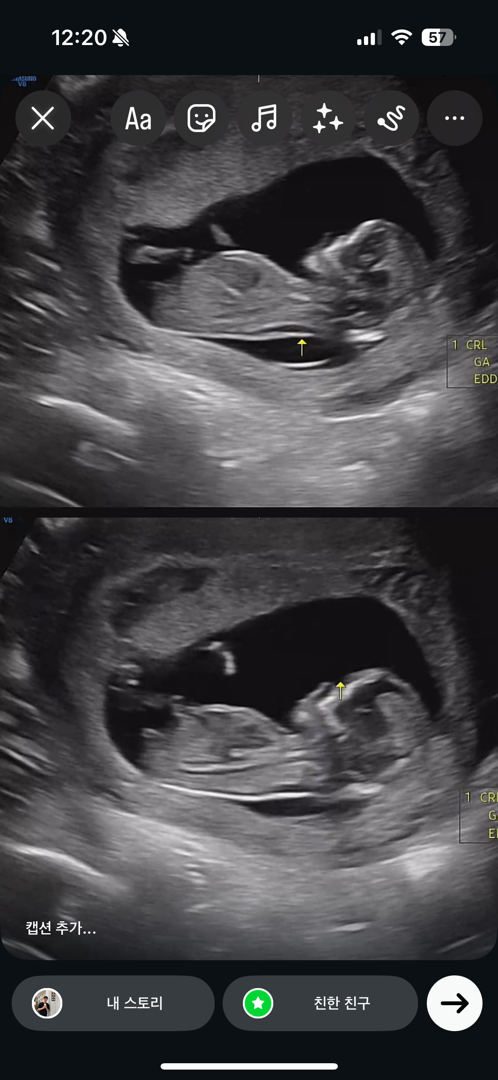

사진은 월요일에 찍은건데 11주 2일이였는데 크기로는 11주 6일로 잡히네요 ㅎㅎ 남녀인지 알수있으려나요..